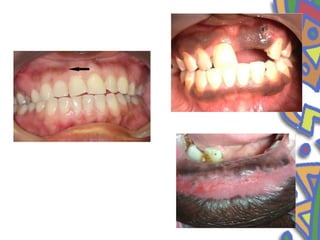

• Commisural lip pit

• congenital or developmental defects

• Their location suggest that they may represent a failure of normal

fusion of embryonal maxillary and mandibular process

• Unilateral or bilateral

• Clinical features

• Invagination is usually 1-2mm in diameter, may be as deep as

4mm and is lined by stratified squamous epithelium

• Folliate papilla

• Occurs as an area of vertical fold and grooves located on the

extreme posterior lateral surface of tongue

• Occasionaly mistaken for tumours or inflammatory disease

• Bilaterally symmetrical

• In some people the papilla are small and inconspicious whereas

in others they are prominent